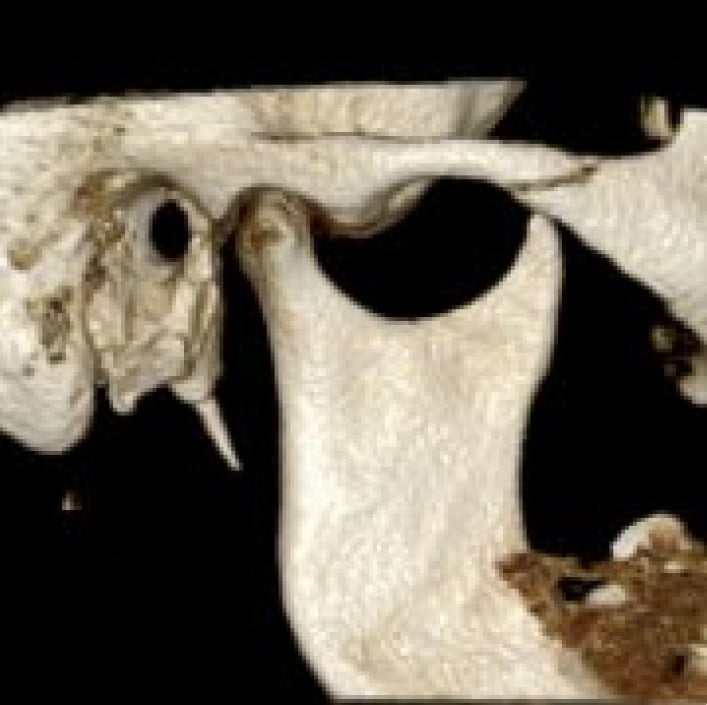

TMJ views and assessment